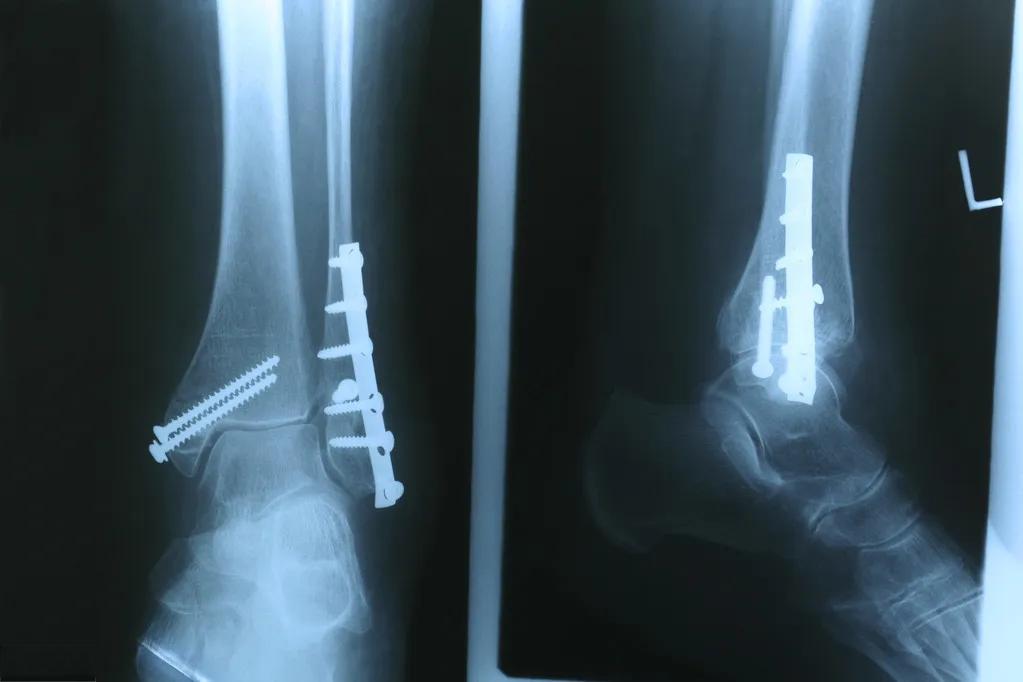

小腿骨折是常见的骨科损伤之一,正确的治疗和康复训练对于恢复腿部功能至关重要。根据骨折的类型和严重程度,治疗方法可能包括保守治疗(如石膏固定)或手术治疗。无论采用哪种方法,康复训练都是不可或缺的一环。